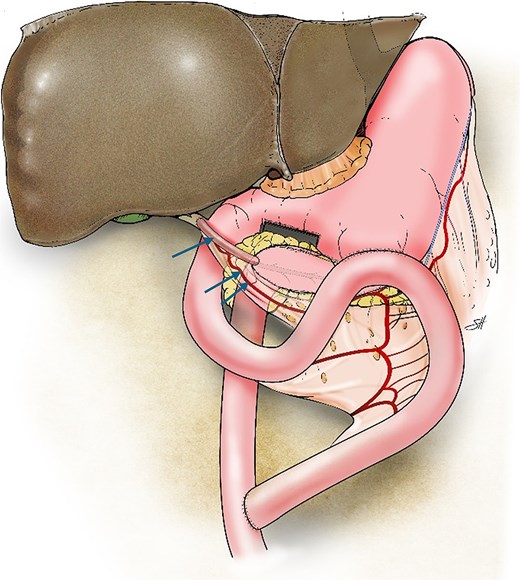

Due to severe inflammation and fibrosis surrounding the duodenum and hepatoduodenal ligament, a hepaticojejunostomy downstream to the PJ could not be safely performed. Therefore, a vascularized gastric tubular graft was fashioned. The greater curvature of the pyloric antrum was stapled ~2 cm from the edge and extended in a cephalad direction, creating a 6-cm gastric conduit while preserving both the right and left gastroepiploic arcades. The conduit was isolated from the stomach at its proximal end by using an Endo-GIA stapler (Covidien, North Haven CT, USA). After adequate perfusion from the left gastroepiploic arcade was confirmed, the right gastroepiploic artery was ligated and divided to allow free conduit mobilization.

The anterior surface of the common bile duct was incised transversely. An end-to-side anastomosis between the common bile duct and the gastric conduit was created by using interrupted 5–0 polydioxanone (PDS) sutures. The distal end of the conduit was then anastomosed end-to-side to the PJ loop in two layers by using 3–0 silk and 4–0 PDS sutures.

Finally, the proximal jejunal limb was used to construct side-to-side gastrojejunostomy on the posterior wall of the stomach by using the Endo-GIA stapling device (Covidien). The jejunojejunostomy was constructed 50 cm distal to the biliary anastomosis (Fig. 2).

Illustration of the triple bypass depicting reconstruction of the Roux-en-Y PJ, loop gastrojejunostomy, and the tubular gastric conduit (single arrow) created from the greater curvature of the stomach while maintaining the left gastroepiploic arcade (double arrows) to complete the end-to-side hepaticojejunostomy.

Here, we highlight a novel triple-bypass technique for managing chronic pancreatitis. We utilized the proximal jejunum to bypass the stomach, pancreas, and bile duct. An isolated vascularized tubular conduit was fashioned from the greater curvature of the stomach to facilitate a safe and tension-free hepaticojejunostomy. The gastric conduit, ~6 cm in length, was created while preserving the left gastroepiploic arcade. Dividing the right gastroepiploic artery allowed for the greater reach of the graft without compromising its blood supply. This maneuver was critical for successful tension-free anastomosis to the common bile duct.